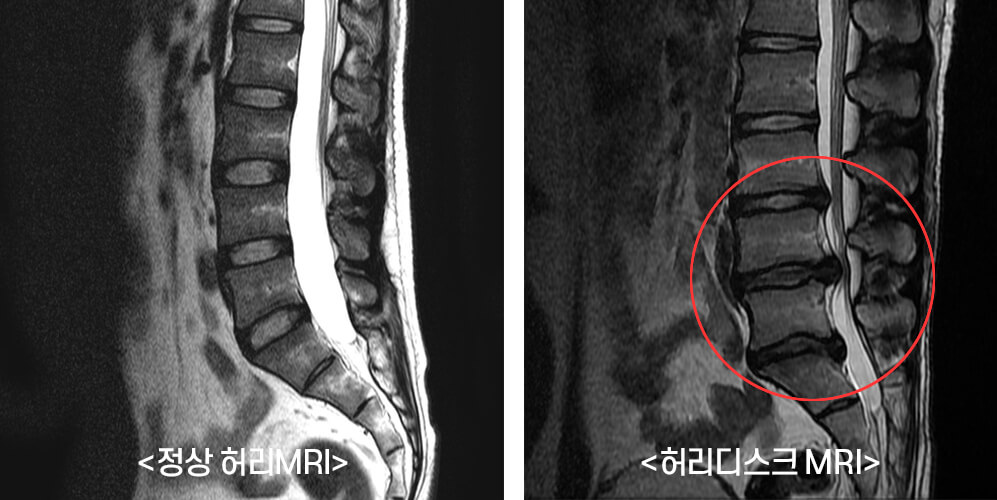

추간판 탈출증이라 불리는 허리디스크 증상은 크게 3단계로 나눌 수 있어요. 1단계는 내부 섬유륜이 파열하여 수핵이 빵빵한 상태, 2단계는 섬유륜 전체가 파열되어 수핵이 탈출하는 단계, 3단계는 완전히 탈출해 버린 단계입니다.

단계마다 느끼는 증상들이 조금씩 다른데요. 디스크의 보호막이 약간 찢어졌고 디스크가 약간 튀어 주변의 신경 뿌리에 닿으면 염증성의 통증이 발생하기 시작하면서 점점 증상이 심해지면 디스크의 파열은 골수를 이루고 있는 핵이 튀어나오면서 신경에 대한 물리적 압박을 가하고 참을 수 없는 아픔을 유발하게 돼요.

디스크의 초기 증상을 살펴보면 추간판 디스크 파열에 비하여 눌리게 된 디스크 양이 많지 않으니, 신경에 대한 물리적 압박이 그다지 심하지 않다고 볼수는 있어요. 하지만 마비 증상과 근력 저하의 증상으때문에 한쪽 다리나 또는 양쪽 다리에 저림이 발생할 수 있어요. 또한 허리주변이 아프거나 허리의 통증을 느끼는게 있다고 합니다. 혹시라도 이러한 증세를 겪고 있다면 디스크의 초기 증상은 아닌지 확인할 필요가 있다고 합니다.